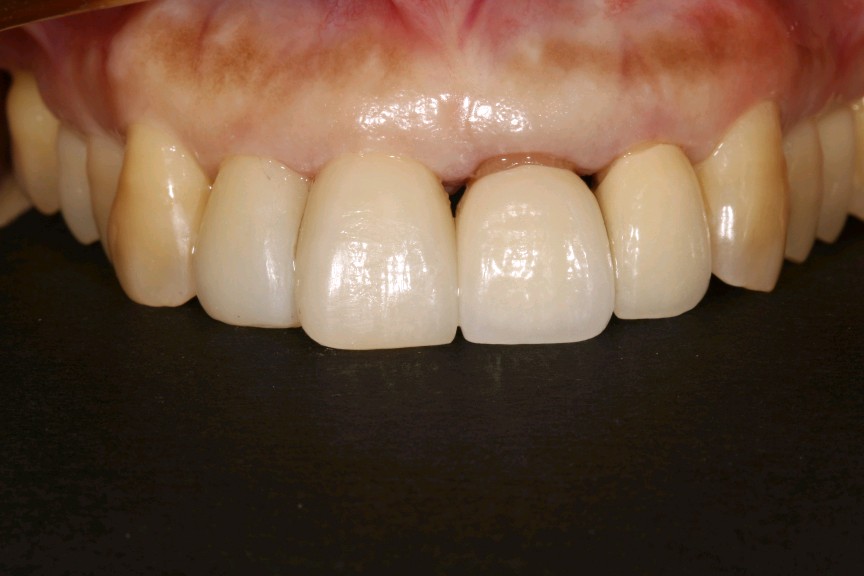

治疗计划:1、牙周治疗。2、21,22饵激光拆除牙冠。清理基牙,重新预备,西诺德全冠修复。3、11、12贴面修复。

这位患者就是错误的刷牙方式,加上牙周炎导致的牙龈萎缩,牙颈部暴露。最终只能拆除重新修复。既费钱又费时间。所以往往一些不起眼的小问题,生活中的一些不良小习惯,日积月累就会出现从小问题发展成大问题。使得前面的工作功亏一篑徒劳无功。一定要谨遵医嘱,使用正确刷牙方式,定期复查,及时发现及时杜绝。